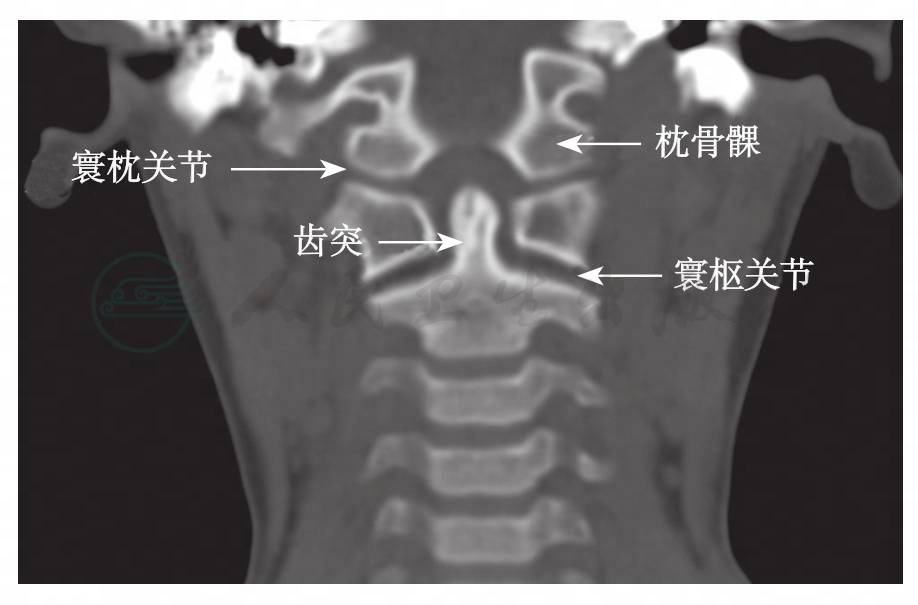

寰枕关节由枕骨髁与寰椎上关节面组成(图1),关节囊以及枕骨大孔与寰椎之间的寰枕前、后膜共同维持关节的稳定性。而枕骨与枢椎之间的覆膜、翼状韧带和齿突尖韧带等也参与维持其稳定性(图2,图3)。关节的过伸运动主要受覆膜的限制,过屈运动则受到颅骨与寰椎前缘的骨性接触限制。侧弯和旋转运动主要受翼状韧带的限制。寰枕关节的活动范围为:屈25°→←伸25°,左右侧屈以及一侧轴向旋转范围均为5°。由于寰枕关节紧邻脑干、脑神经及椎动脉,如骨折同时造成这些结构的损伤,可导致部分病例在得到救治之前死亡。但有些经过抢救幸存的患者中,经过治疗后甚至能够完全康复。该病在儿童的发生率大于成人,由于儿童的枕骨髁发育未完善,寰枕关节面较平坦且易脱位,其关节周围的韧带较为松弛,因此其关节的稳定性较差。

图1 正常枕骨髁冠状面CT重建